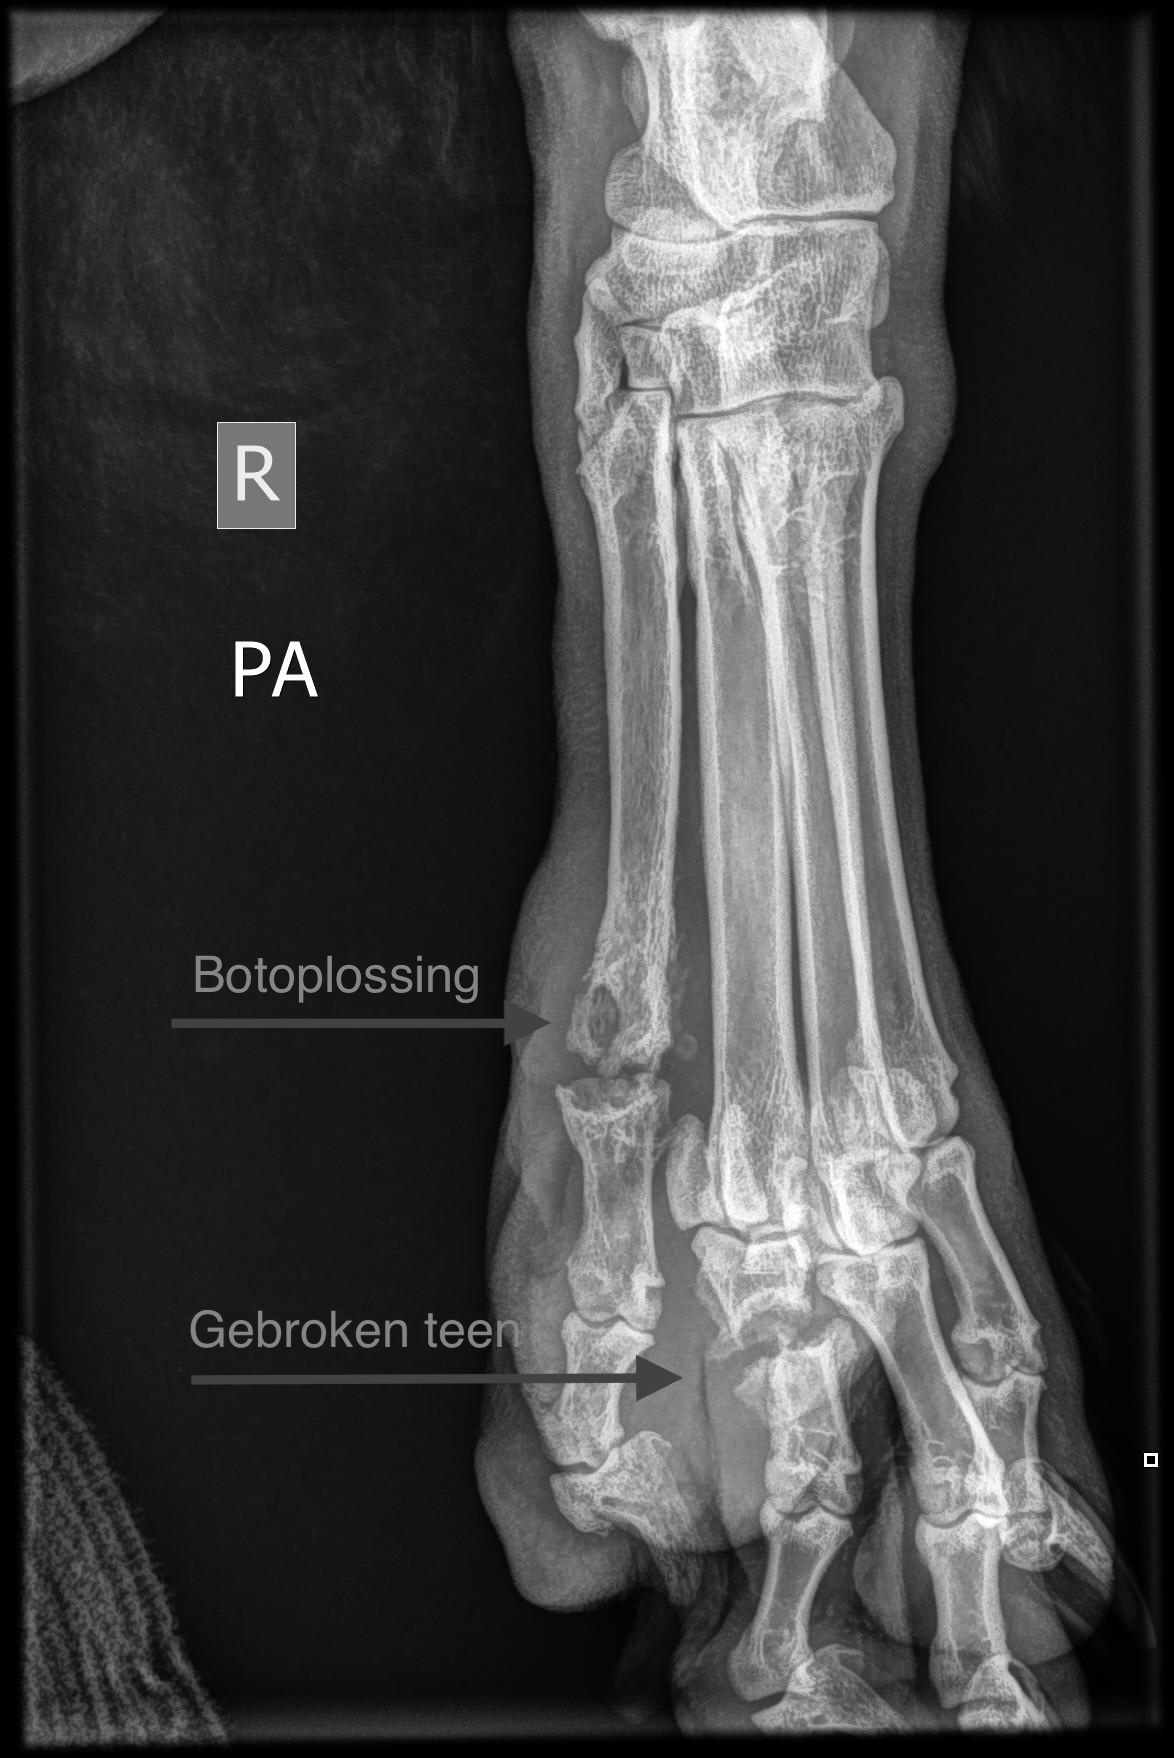

Maar tot onze schrik zagen we op de röntgenfoto ook dat een teenkootje van de andere teen gebroken was. Als hij een teen mist, zal deze gebroken teen harder moeten werken. We hadden nu twee problemen: een fistelende teen met bacteriën (te zien aan het contrastmiddelverloop) en een gebroken teenkootje. We gingen aan de slag: de teen werd verwijderd en een spalk voor de ondervoet werd aangemeten. Het gebroken kootje kon daardoor rust krijgen en gaan helen, terwijl we de operatiewond konden verbinden.